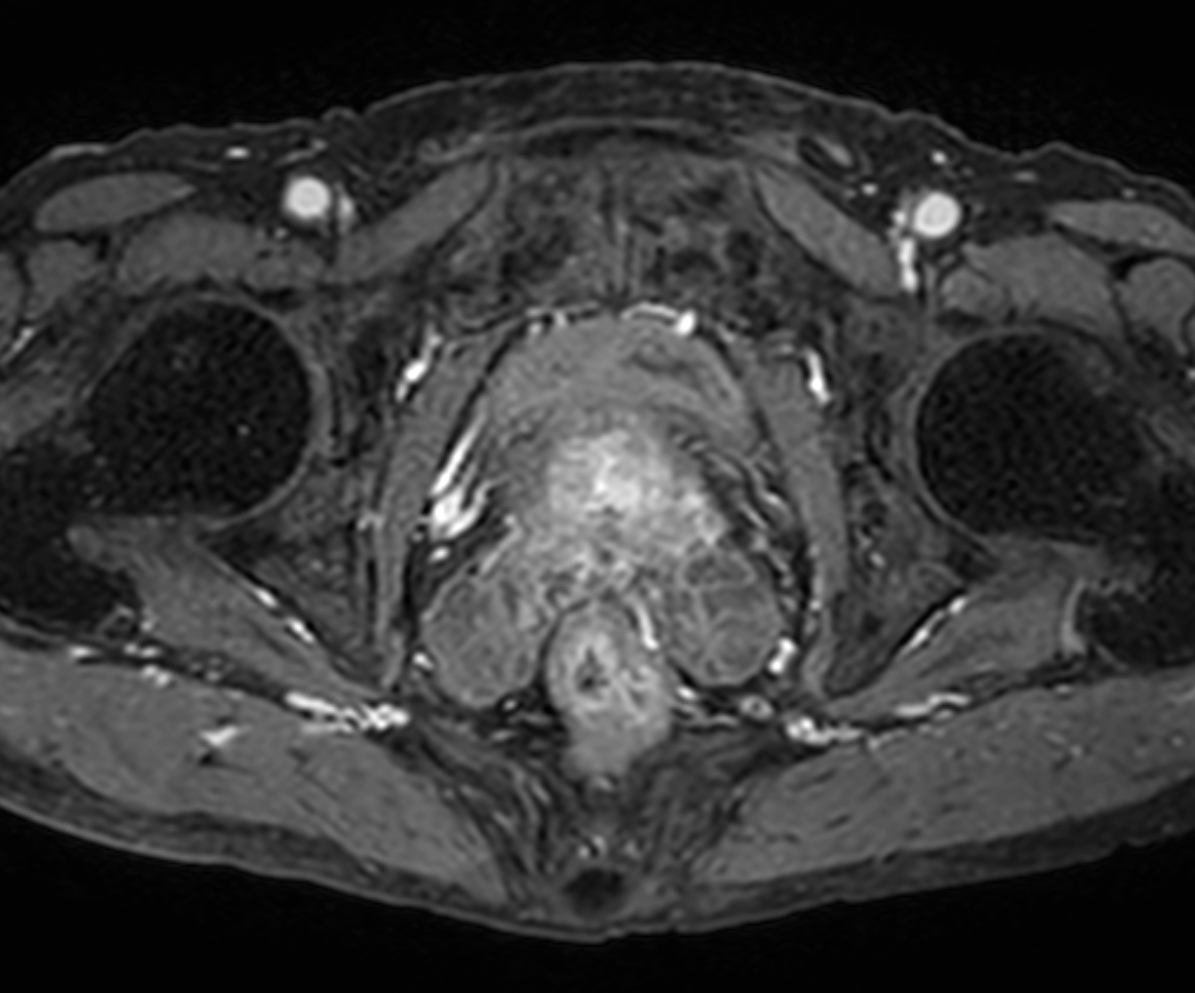

Axial DWI (b1000, ADC)